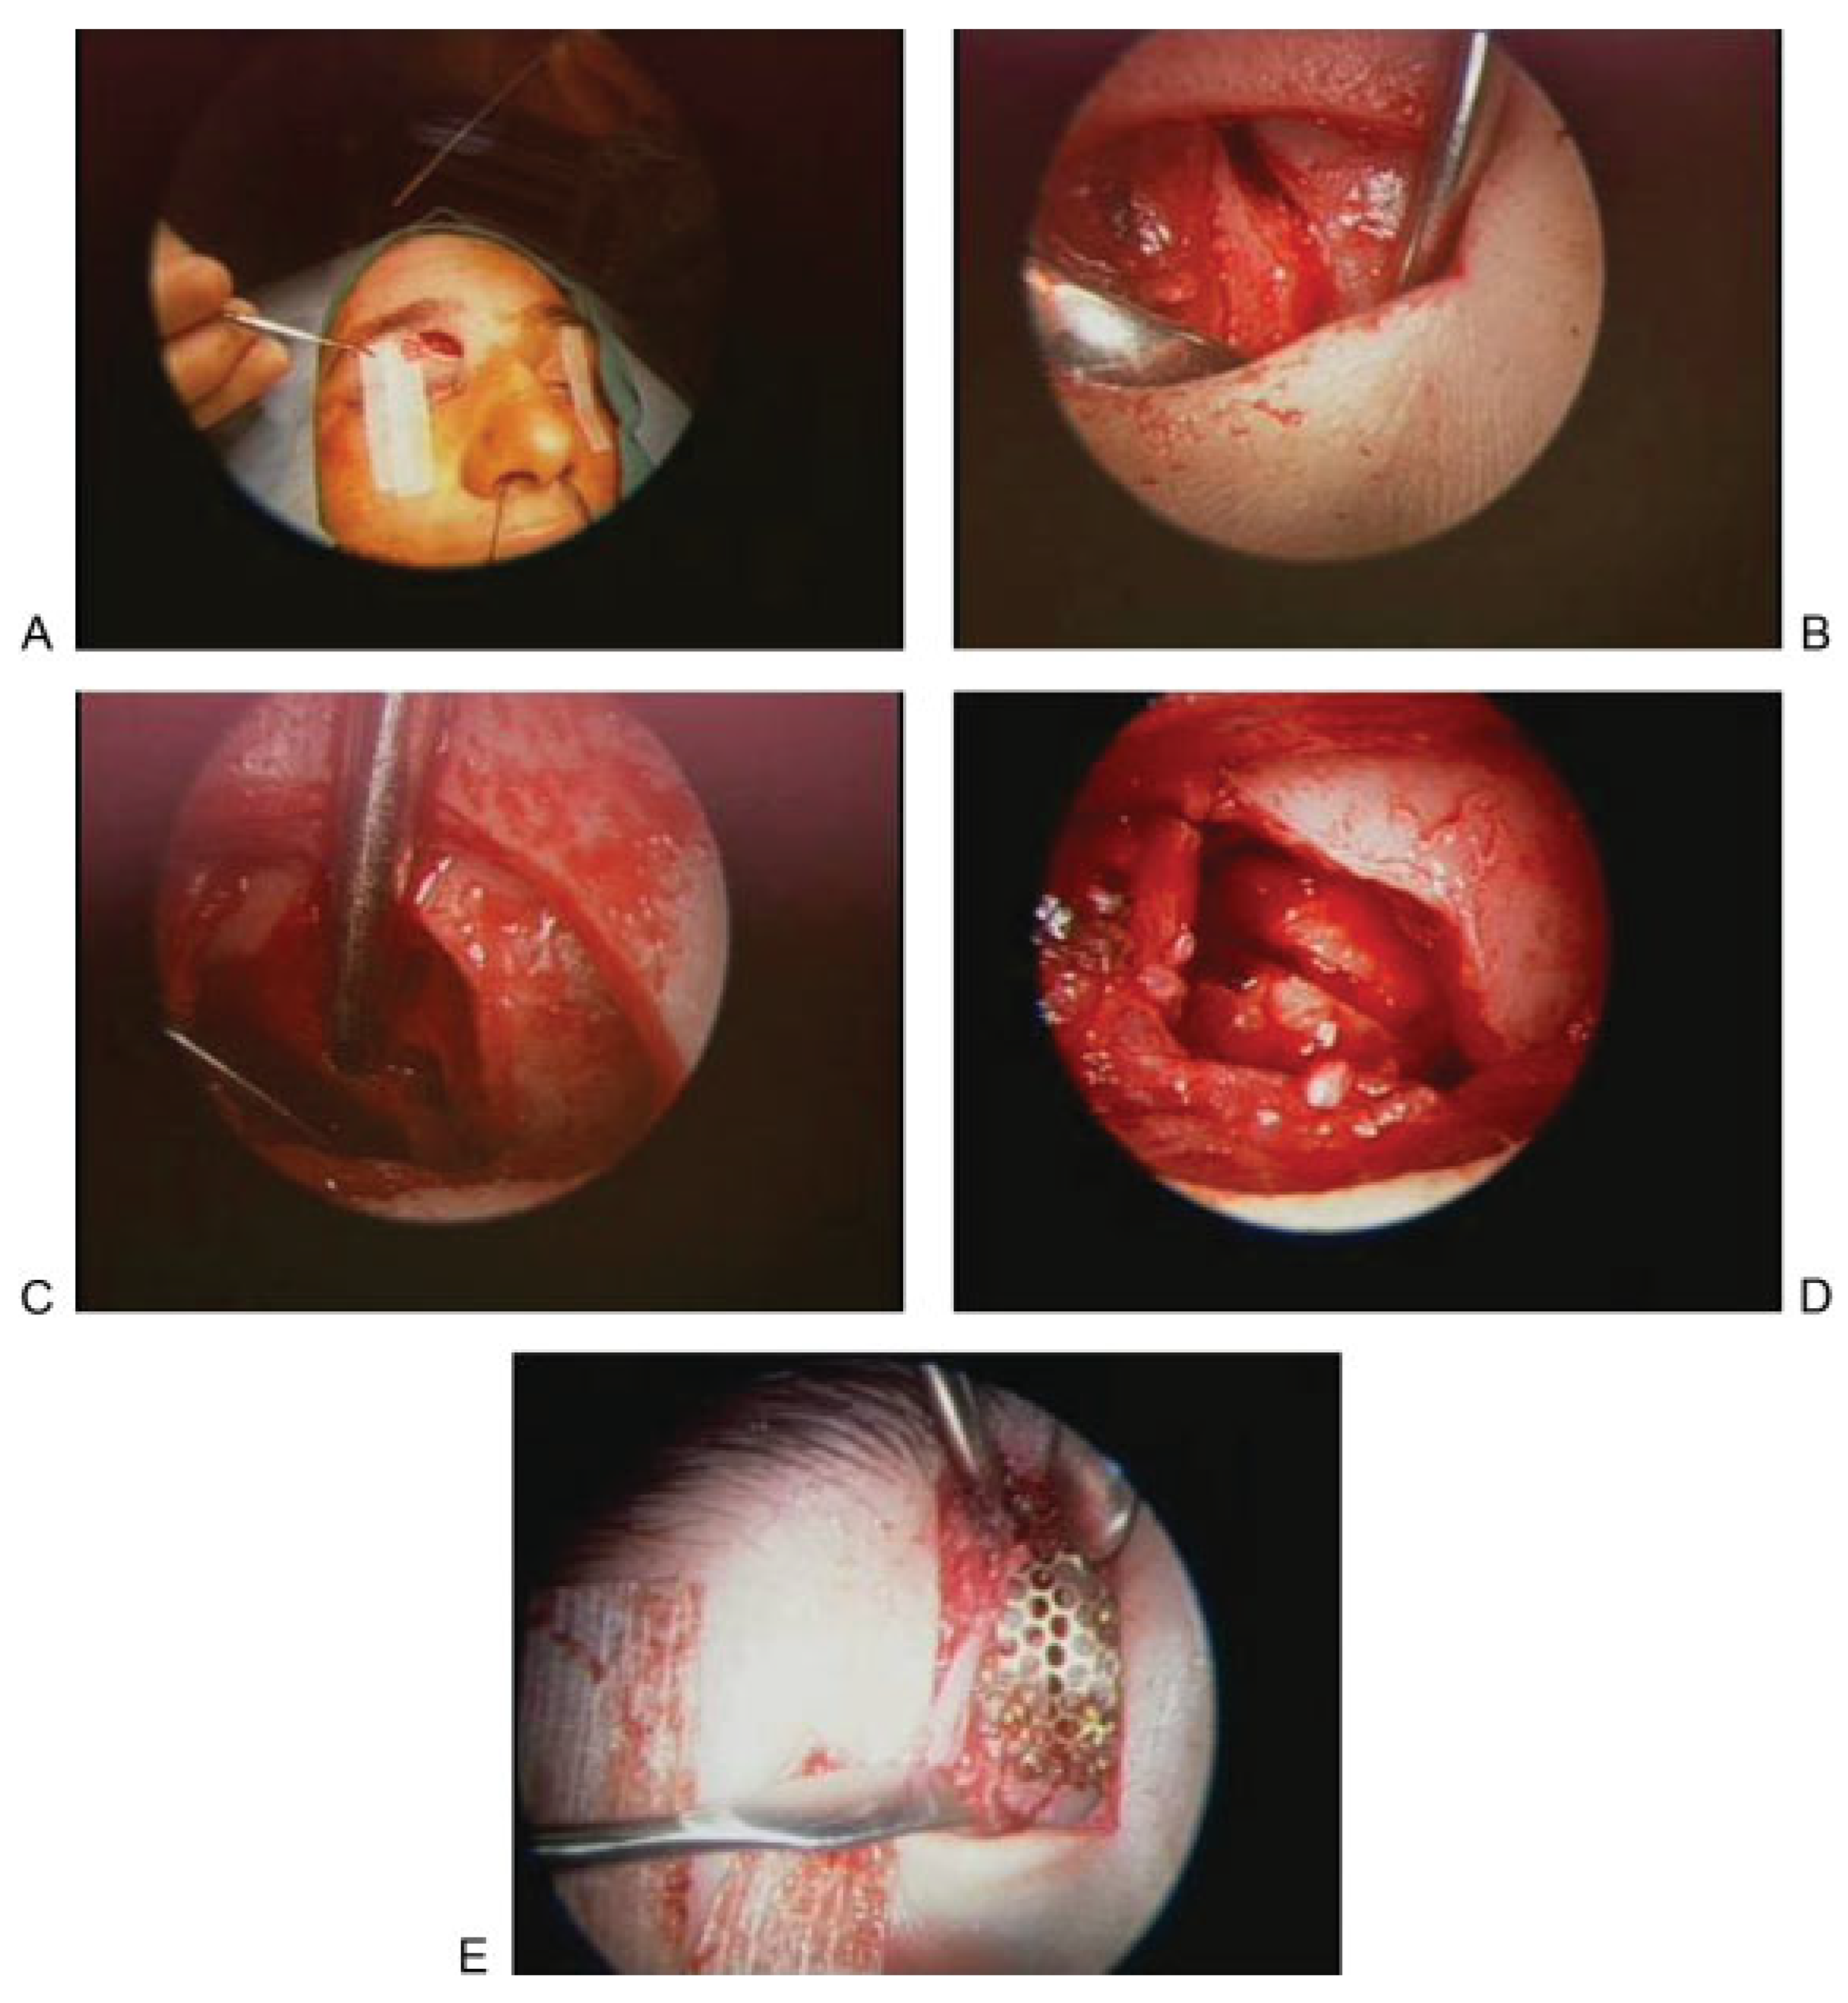

Endoscopic camouflage allows for restoration of the frontal contour in the absence of fracture reduction. Endoscopic camouflage is a useful technique that has been advocated by Kellman and Strong [15,17]. The camouflage approach offers two main advantages, in that it not only avoids large incisions and exposures (and therefore qualifies as a more minimally invasive technique), but it also allows for delayed intervention. This provides the particular advantage of waiting to see if the depression due to the fracture will be severe enough to justify intervention. This is in contrast to the reduction approach which requires repair before the bone healing in the malaligned position. Materials that have been advocated for the camouflage technique include porous polyethylene, titanium mesh, and hydroxyapatite cement [15,17]. Figure 3 shows CT and intraoperative images from a patient treated with the endoscopic camouflage technique for a depressed left frontal sinus fracture.

Figure 3.

(A)Axial computed tomographic image showing depression related to an anterior table fracture. (B–E) Intraoperative photographs showing repair of frontal depression related to an anterior table fracture. (B) After making an incision, (C) an endoscope is used to dissect in the subperiosteal plane and expose the depression. (D) Hydroxyapatite cement is then injected and gentle pressure is used to smooth the cement to restore the appropriate contour. (F) Axial postoperative image showing excellent restoration of the frontal contour after placement of bone cement.